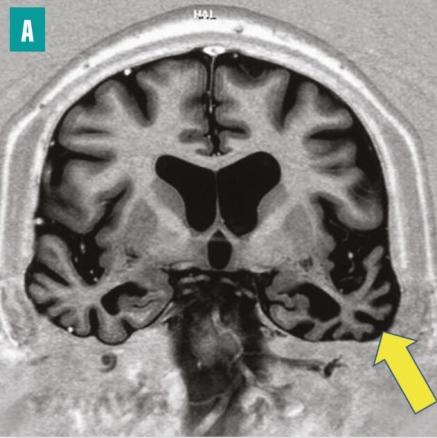

IRM cérébrale en séquence d’inversion-récupération, coupe coronale. Atrophie du cortex temporal prédominant à gauche, dont témoigne l’élargissement des sillons corticaux (flèche)